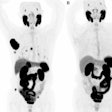

The Bothell, WA-based Philips’ Gemini PET/CT is comprised of its Allegro PET with gadolinium oxyorthosilicate (GSO)-based detectors and the option of either dual-slice or 16-slice CT options. The product comes with multimodality DICOM connectivity and radiation oncology simulation options, Philips said.

Also being shown in the PET family is Mosaic, a new small-bore animal imaging system, which is making its RSNA debut. Both the Mosaic and Gemini systems are available now.